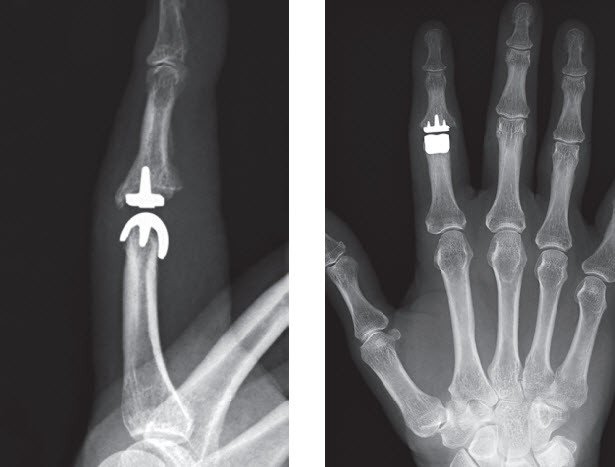

Um eine breite Dokumentation und Nachkontrolle neuer Prothesen und Behandlungsmethoden zu gewährleisten, arbeiten wir eng mit der wissenschaftlichen Abteilung zusammen. Dies erlaubt uns, Früh- und Spätkomplikationen zu erfassen und bei Bedarf entsprechende Massnahmen zu ergreifen oder die Wirksamkeit neuer Operations- / Therapiemethoden zu belegen. Hierfür werden neben der klinischen Kontrolle auch international anerkannte Patientenfragebogen, wie zum Beispiel den Michigan Hand Outcomes Questionnaire, abgegeben. Diese werden von den Patienten vor und nach einem Eingriff ausgefüllt und geben einen Überblick über die Beschwerden und Fähigkeiten, bestimmte Tätigkeiten auszuführen. Die Zusammenarbeit mit der Forschungsabteilung ermöglicht uns auch die Entwicklung und die Nachkontrolle eigener Kunstgelenke, wie zum Beispiel der seit 2010 eingesetzten Oberflächenersatzprothese für Fingermittelgelenke (CapFlex®).

- Gelenkersatz an Hand- und Fingergelenken